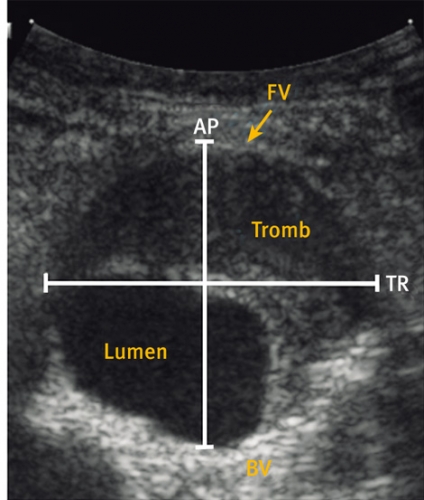

Ultraljudsundersökningen vid screening (Figur 2) skiljer sig från en fullvärdig aortaundersökning såtillvida att dess primära syfte är att med hög säkerhet utesluta sjukdom. Vid screening läggs transduktorn i kärlets längsriktning (Figur 2 a) och maximal infrarenal anteroposterior diameter mäts enligt principen »leading edge to leading edge« (Figur 3). Måttet anges på ett protokoll, som också innehåller uppgifter om eventuella visibilitetsproblem samt undersökarens initialer. Vid diameter ≥25 mm anges också diametern med transduktorn vinkelrätt mot kärlet (Figur 2 b).

I samma seans görs då också en utvidgad undersökning omfattande diametern av »aortahalsen« (segmentet nedanför njurartärernas avgång) och den suprarenala aortadiametern, för att få en uppfattning om den relativa diametern, samt av iliaca-kärlen. Samtliga mätningar (såväl positiva som negativa) dokumenteras genom en pappersutskrift.